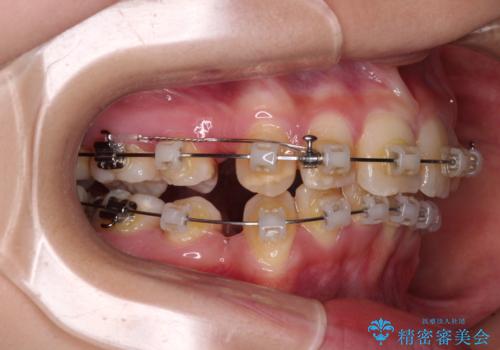

- クリアブラケット

- 2年9ヶ月

- 前方に飛び出した前歯と、下顎の八重歯を気にして来院された患者様です。

口元の突出感を改善するため、上下左右の第一小臼歯4本を抜歯し、ワイヤー装置にて矯正治療を行うこととしました。